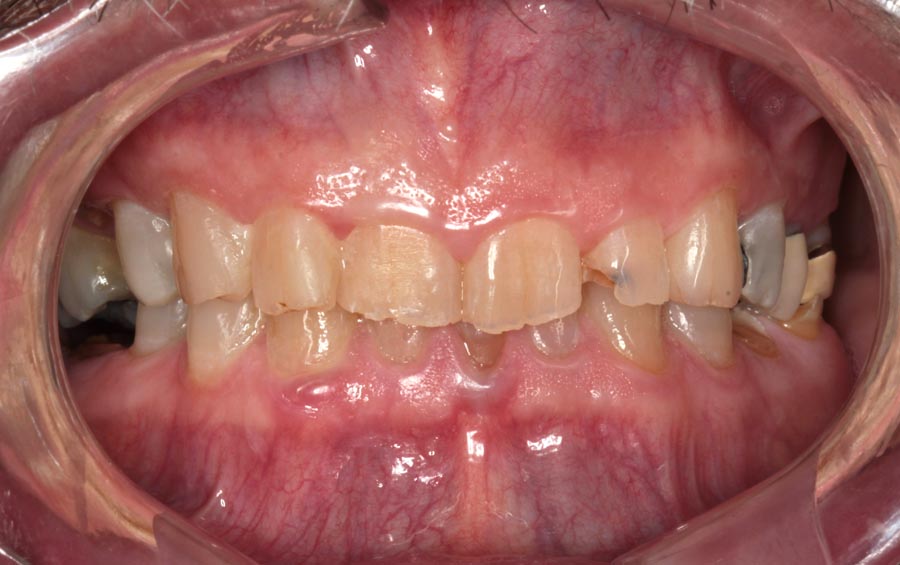

Patient wanted to see what longer, prettier teeth would look like. Crown preparations to prepare for crown lengthening and temporary crowns/bridge.

This is known as hard (bone) and soft tissue (gums) crown lengthening. To have loner teeth, many patients need their bone recontoured so that the gums do not grow back down to their original position.

The patient returns six months later without his temporary bridge. His grinding caused their destruction. He was saving money for implants. He decided that he would rather have full mouth implants because he believed that his tooth would eventually fail if he saved them now. And he believed he could only afford this treatment once in his life. I agree with all these beliefs, for him. And we gave him six months to ponder his decision.